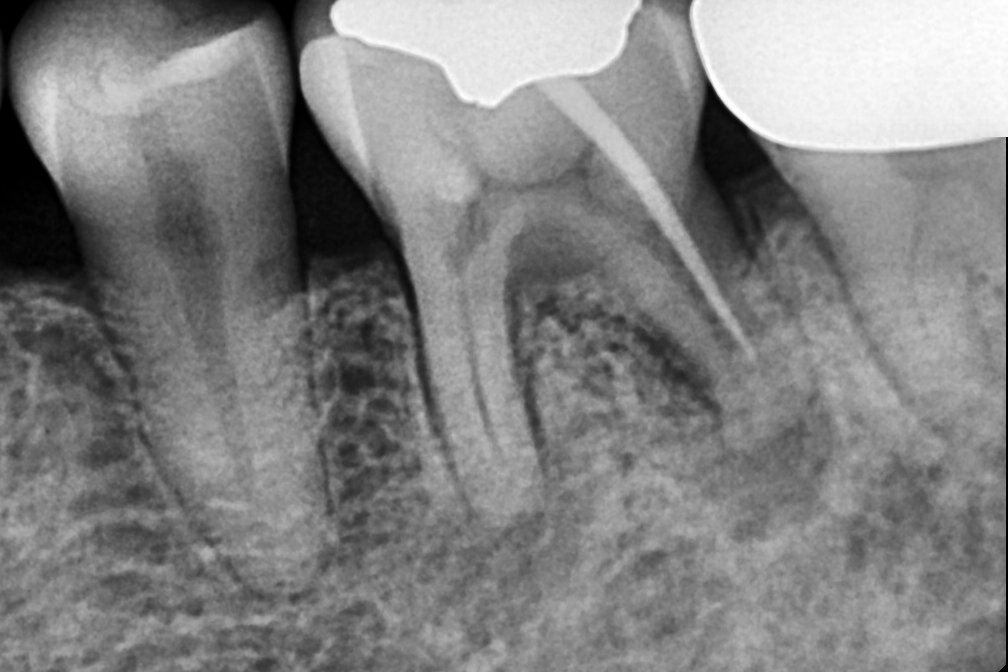

신경치료

Before 2025년 11월 25일

After 2026년 4월 11일-

위 전후사진은 이미지사진으로 실제 눈으로 보는 것과는 다를 수 있으며, 환자의 치아상태과 방법에 따라 치료결과가 다를수 있습니다.

사진의 날짜는 촬영날짜이며 치료의 기간이 아님을 알려드립니다.

치료 후 치아표면의 탈회 , 충치, 치근흡수 등의 부작용이 있을 수 있습니다.